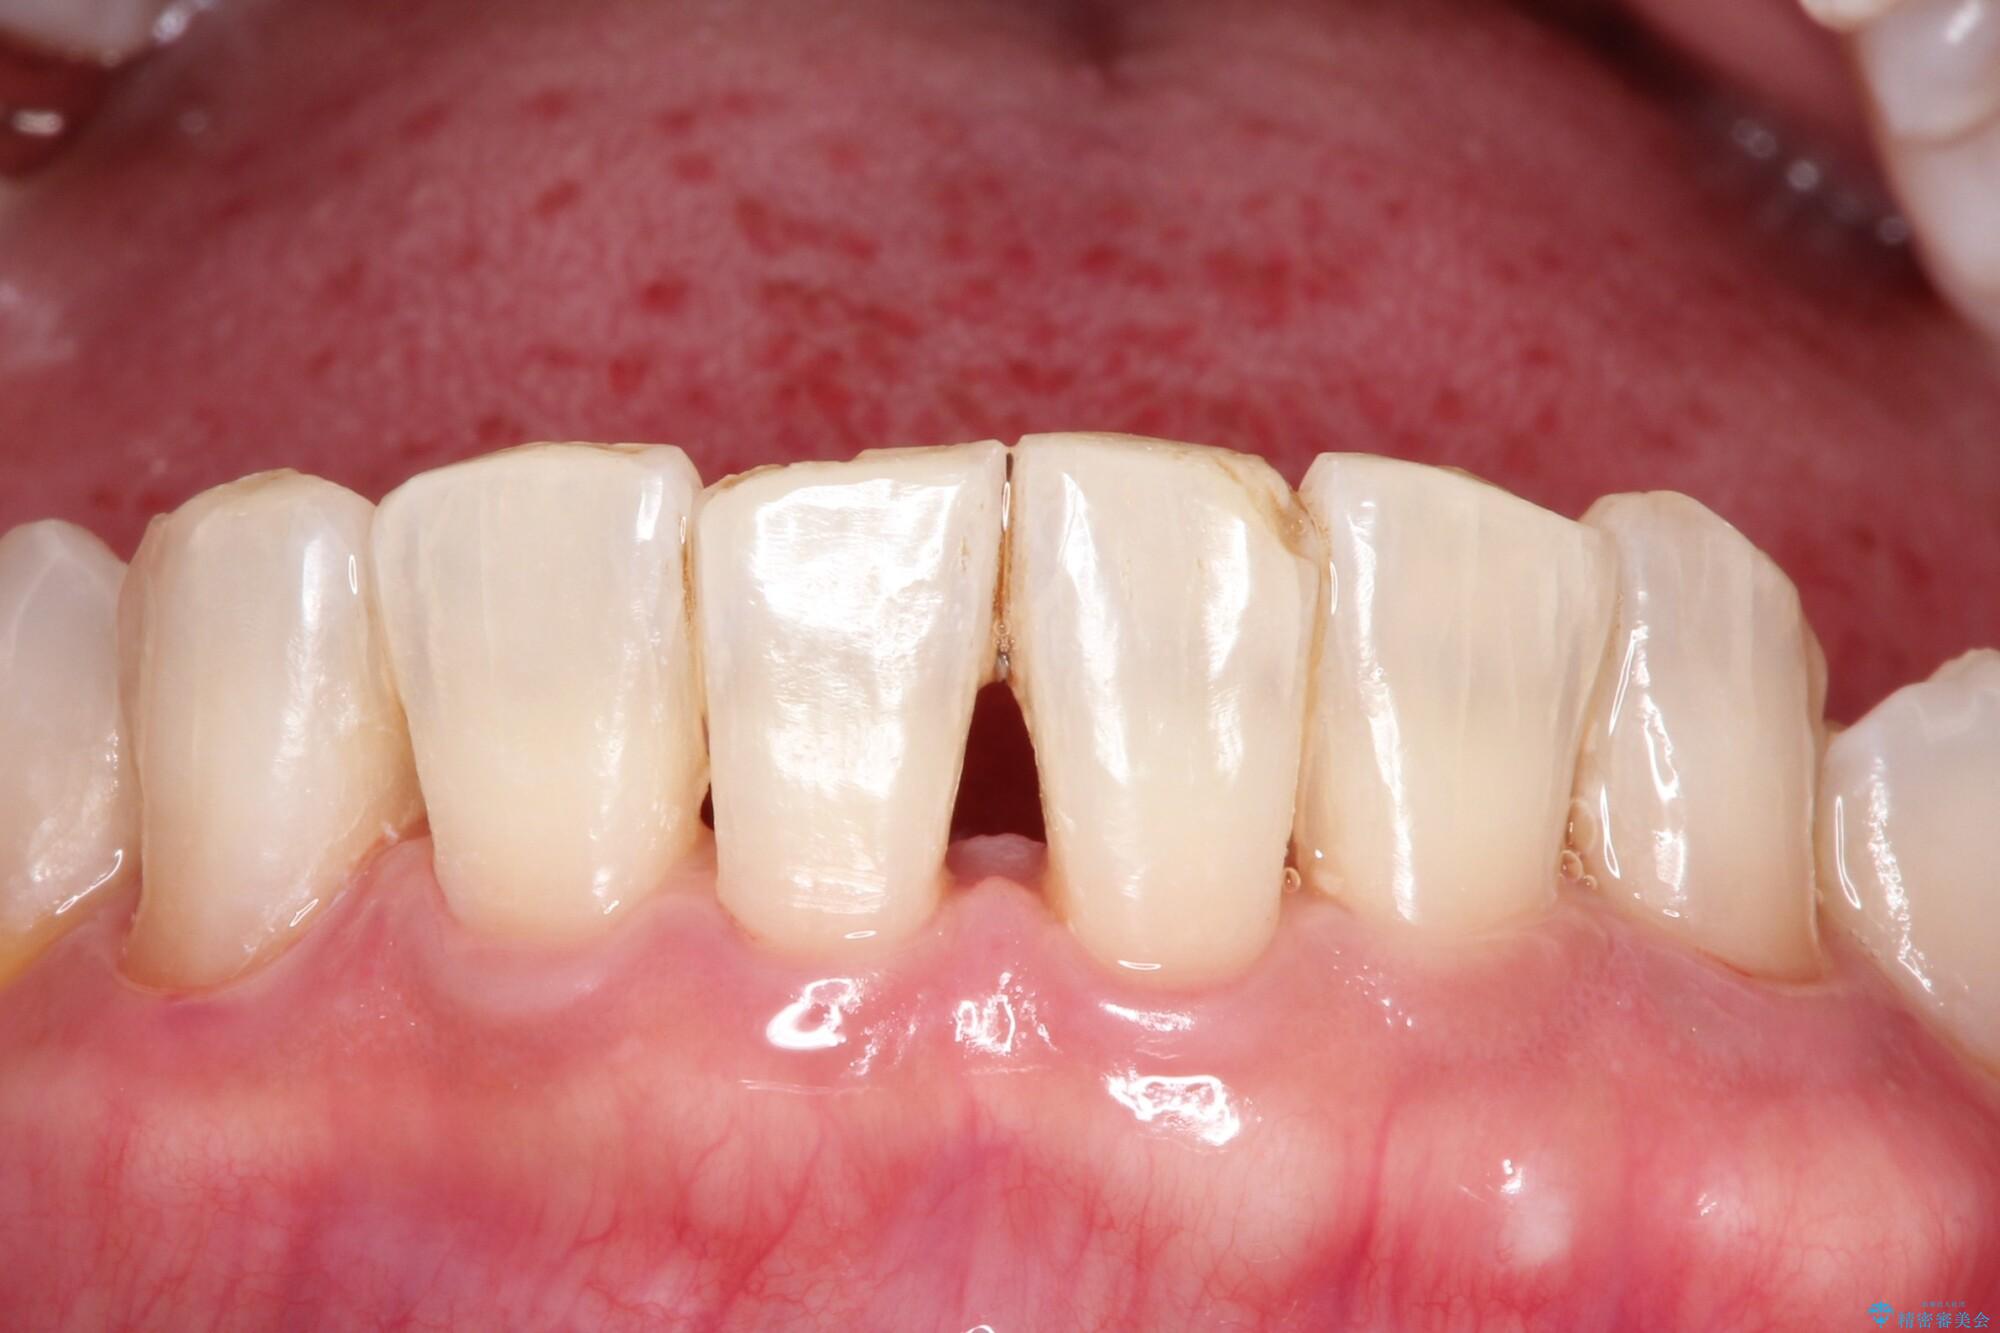

- 久々のクリーニングで来院されました。歯の表面のステイン付着と、下顎前歯に歯石がみられました。今回はPMTCをおすすめしました。

ステインを除去したことで全体のトーンが明るくなりました。下顎前歯は歯石で埋まってしまっていたため、クリーニング後はスペースができたように見えますが、歯本来の形へ戻りました。